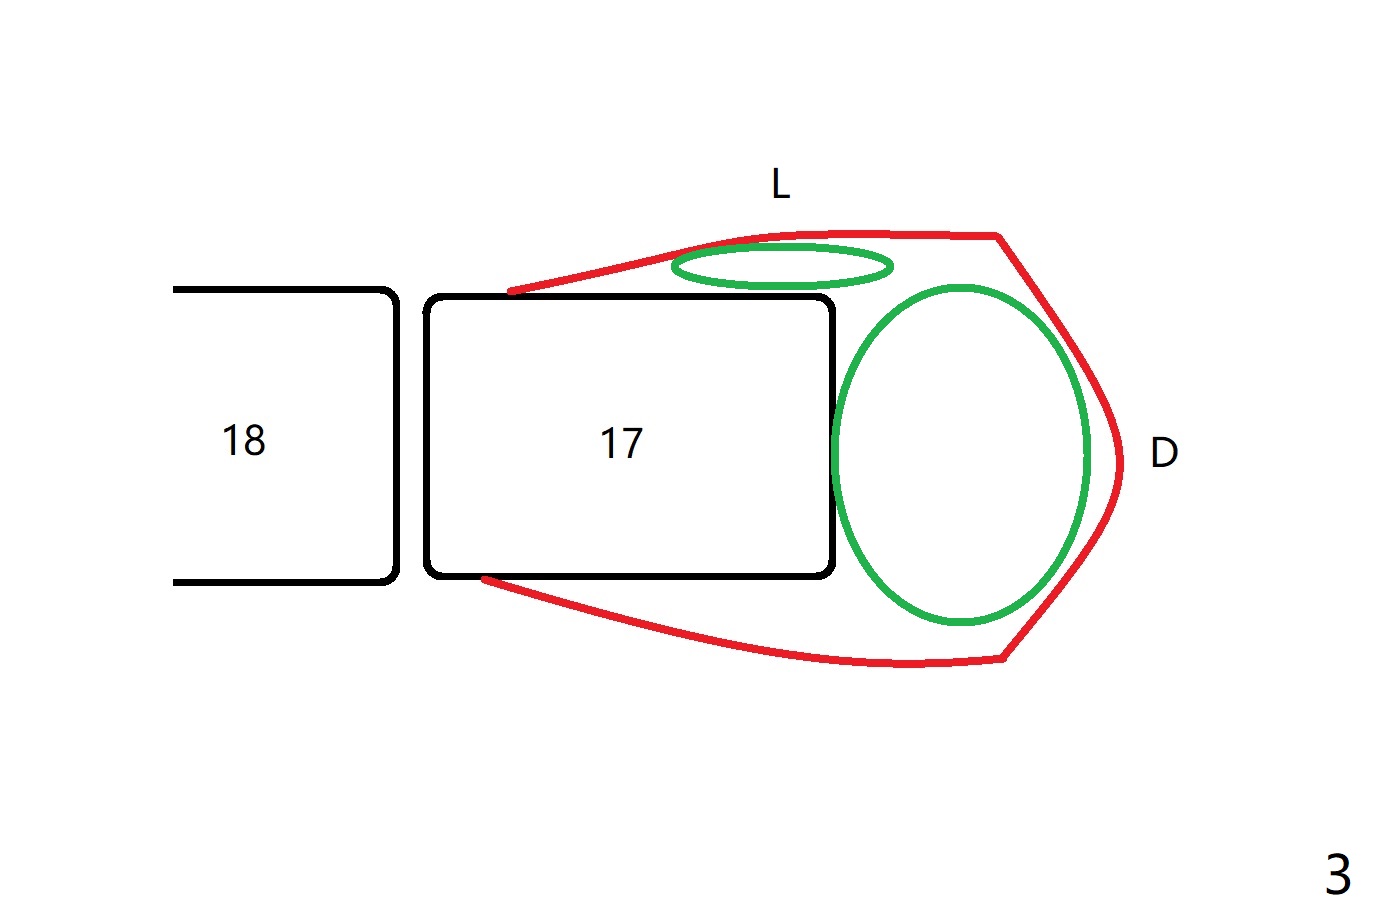

A 20-year-old woman requests extraction of #17 with distal bony defect (Fig.1 *). Since #17 and 18 are close to each other (as compared to the other case), small elevator is not initially inserted between them without incision. The elevator slides distal (Fig.2 (occlusal view)). Incision has to be made for better vision. In spite of block anesthesia, pain is severe. When local anesthetic is being injected into the lingual gingiva, the patient is shivering. As the tooth is removed, a large piece of granulation tissue is attached to the tooth (Fig.3 D (green circle)), while a small piece of granulation tissue remains to the lingual wall of the socket (L (green oval)). After debridement and irrigation, a piece of Osteogen Plug is placed, followed by 5-0 Chromic gut suture.